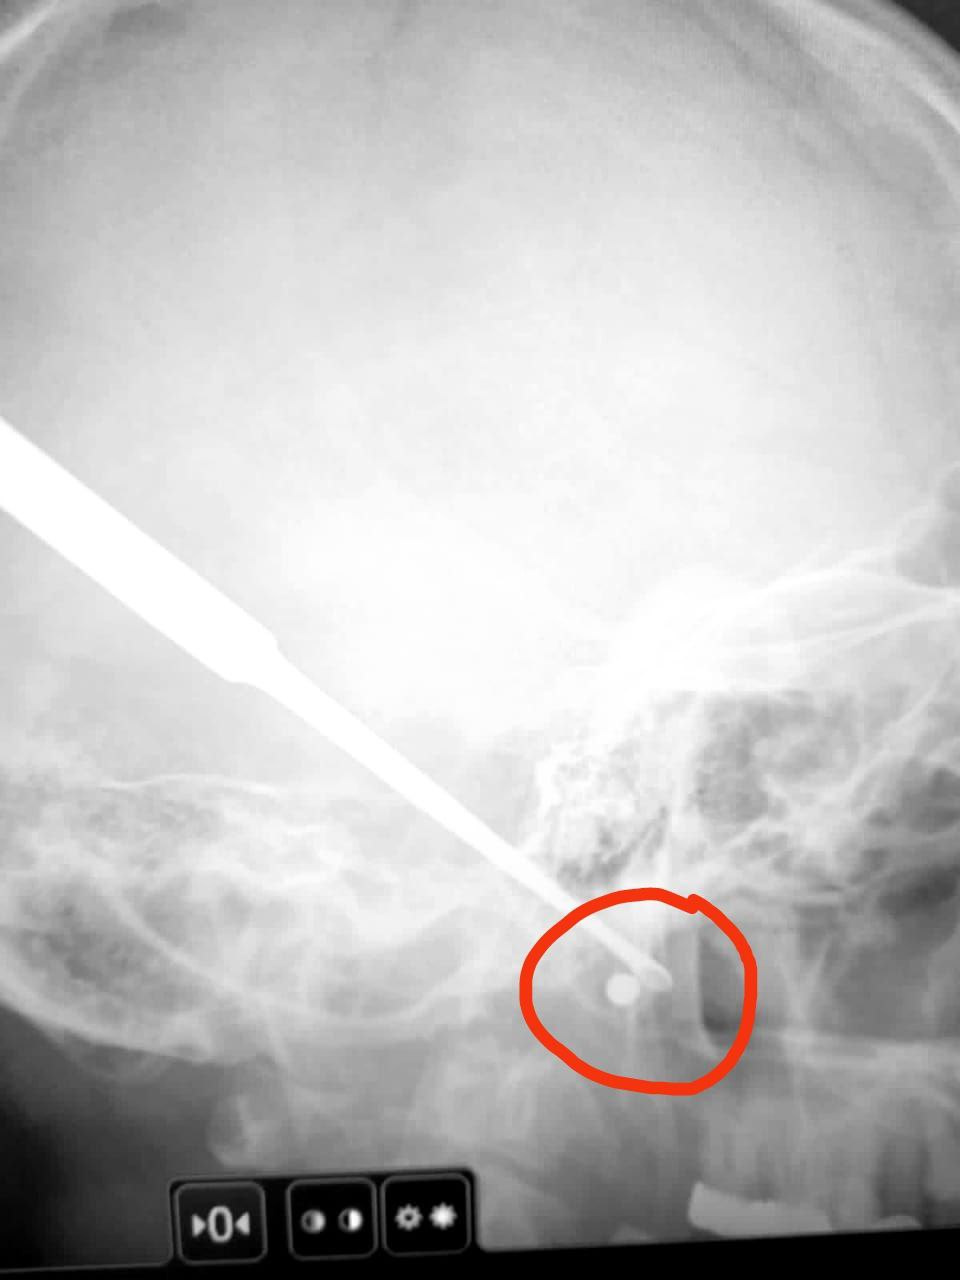

Очевидцы вызвали скорую. Пострадавшего привезли в отделение челюстно-лицевой хирургии, где ему провели сложную операцию. В больнице уточнили, что пневматические пули очень маленькие и они не магнитятся, так что найти и достать их с помощью магнита не получится. В итоге пулю нашли с помощью КТ. А операция, которая длилась несколько часов, проходила с использованием рентгеноконтрастного препарата. Ее провели хирурги Игорь Талтаев, Кирилл Лыков и Диана Аюпова, а также команда анестезиологов.